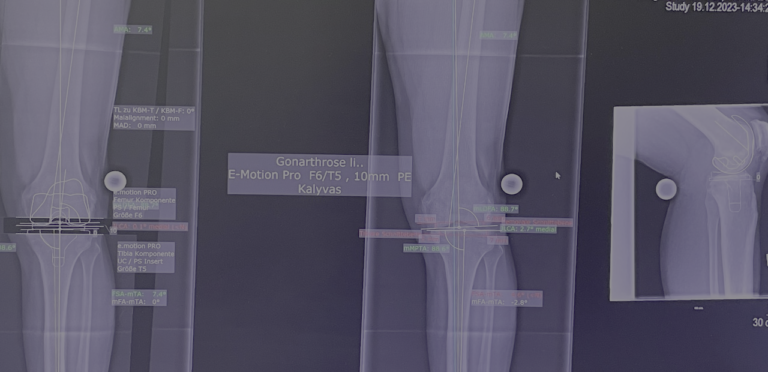

Τεχνική & εξατομίκευση

Η επιλογή της τεχνικής και της πρόθεσης γίνεται εξατομικευμένα, λαμβάνοντας υπόψη:

• την ηλικία

• το επίπεδο δραστηριότητας

• την ανατομία του γόνατος

• τον βαθμό φθοράς

• τα συνοδά προβλήματα υγείας

Στόχος είναι η σωστή ευθυγράμμιση, η σταθερότητα και το φυσικό εύρος κίνησης.

Σημαντική επισήμανση

Η τελική επιλογή της χειρουργικής τεχνικής γίνεται μετά από αναλυτική κλινική αξιολόγηση και προσεκτικό προεγχειρητικό σχεδιασμό, με στόχο το βέλτιστο και ασφαλέστερο αποτέλεσμα για τον ασθενή. Απαραίτητη προϋπόθεση για την επίτευξη εξαιρετικών αποτελεσμάτων αποτελεί η εξειδίκευση του χειρουργού στη συγκεκριμένη τεχνική, καθώς και η εκτεταμένη εμπειρία με μεγάλο αριθμό επεμβάσεων. Ο έμπειρος ορθοπαιδικός χειρουργός κ. Νικόλαος Καλύβας εφαρμόζει την ολική αρθροπλαστική γόνατο επί σειρά ετών στη Γερμανία, έχοντας χειρουργήσει μεγάλο αριθμό ασθενών. Τα τελευταία χρόνια, από τη θέση του Αναπληρωτή Διευθυντή σε ένα από τα μεγαλύτερα κέντρα αρθροπλαστικής της Γερμανίας, είχε ενεργό ρόλο στην εκπαίδευση ειδικευομένων ορθοπαιδικών στη συγκεκριμένη τεχνική.